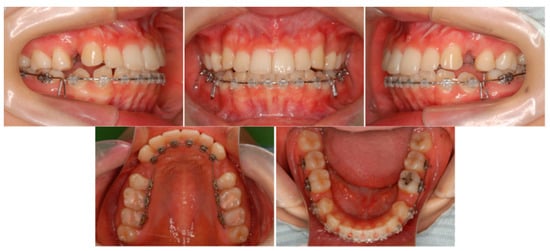

6.2. Treatment Objectives

6.3. Treatment Alternatives

6.4. Treatment Progress